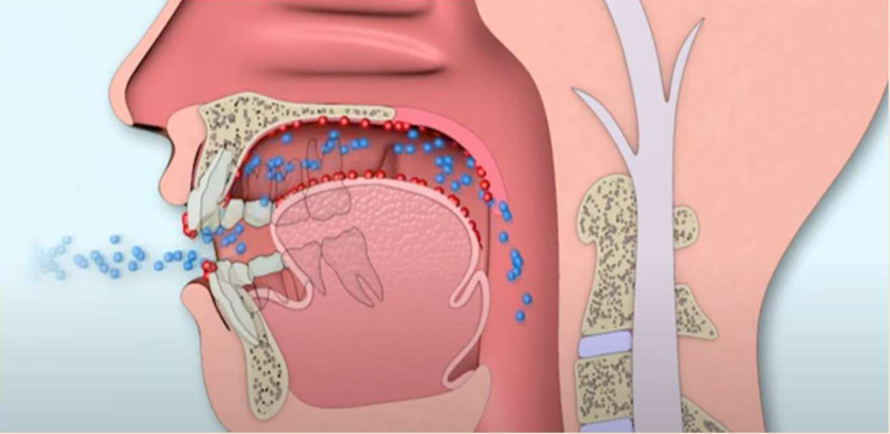

口呼吸と鼻呼吸について

❌ 口呼吸(低位舌)

風邪をひきやすくなる

・細菌やウイルスなどの異物が直接喉に入る

・冷たい乾燥した直接体内に入る

虫歯や歯周病になりやすくなる

・口の中が乾くことで細菌が繁殖しやすい

疲れやすい身体になる

・体内の『二酸化炭素濃度』が薄くなる

・動脈が細くなったり、赤血球が酸素を離さない

・状態になり全身が酸素不足になる

姿勢が悪くなる

・ 頭が前に倒れて体が引けて猫背になる

⭕️ 鼻呼吸

免疫力が高まり風邪をひきにくくなる

・ 『鼻毛』がウイルスなどの異物をブロック

・『鼻腔粘膜・扁桃リンパ組織』がさらにブロック

・ 外からの空気の加温・加湿することで乾燥を防止

疲れにくい身体になる

・ 鼻の中の『気道抵抗』により深い呼吸になる

・『副鼻腔粘膜』から一酸化窒素が分泌される

血管を拡張して酸素を全身へ行き渡らせる

姿勢が良くなる

・『横隔膜』を使った深い呼吸が姿勢を整える